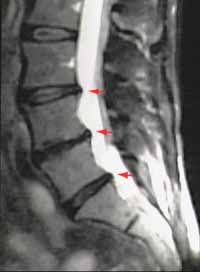

MRI

Prolaps auf der Höhe L4-L5

Beim MRI, auch Kernspintomographie genannt, werden im Gegensatz zum CT keine Röntgenstrahlen verwendet. Es kann die Wirbelsäule mit eventuellen Vorwölbungen der Bandscheiben in den Spinalkanal im Querschnitt und zusätzlich auch im Längsschnitt darstellen. Es ist vor allem in der Darstellung des Nervensystems und der Weichteile, also gerade der Bandscheiben und der Nervenwurzeln, dem CT überlegen.